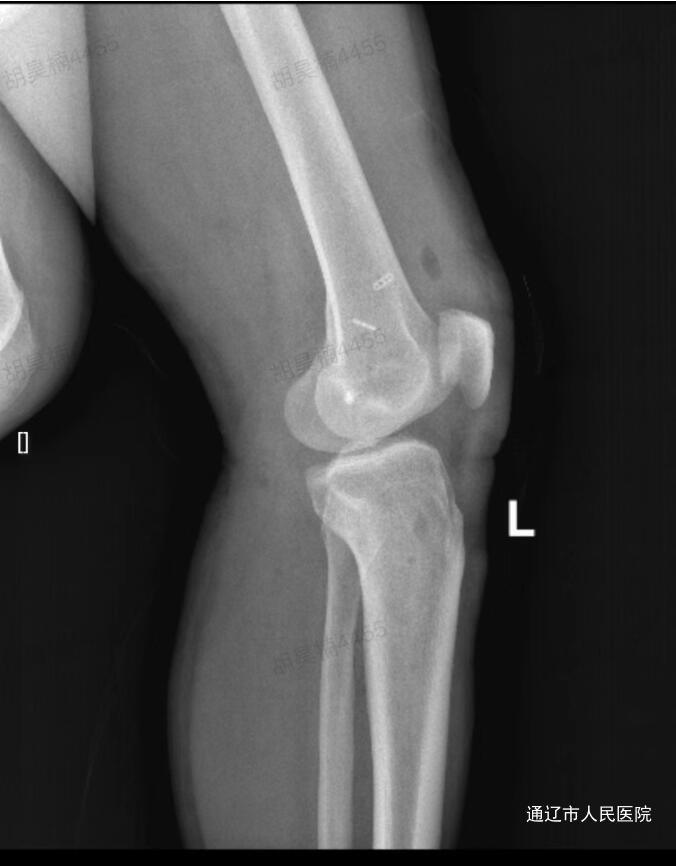

术后